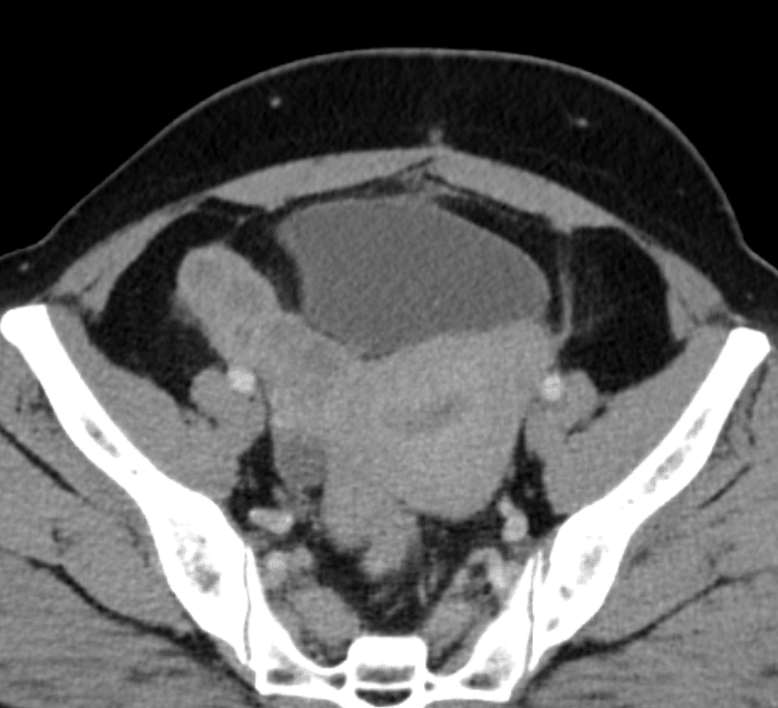

- Radiology: TOA